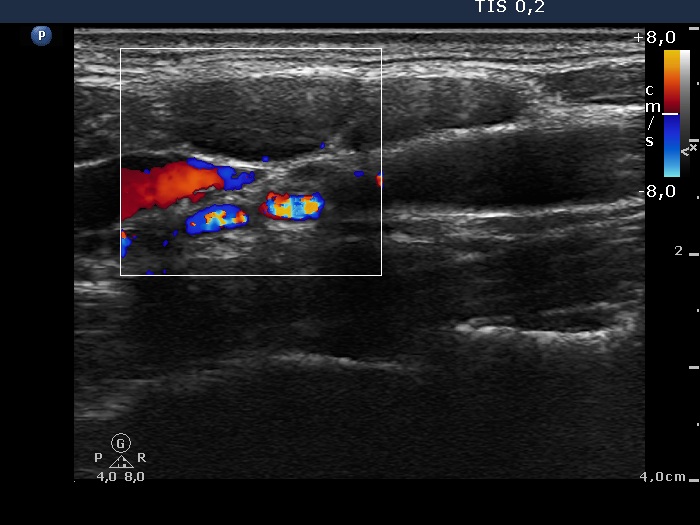

Left submandibular area of the neck, longitudinal scan, color Doppler mode. Two lymph nodes next to each other.